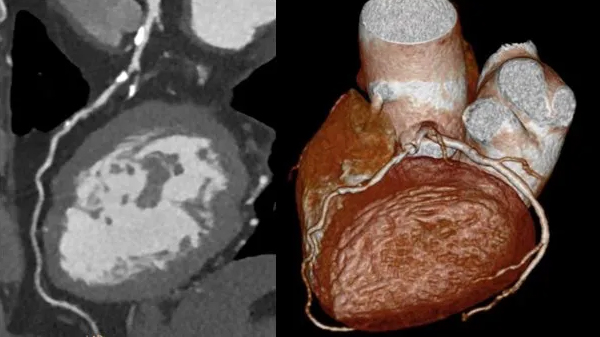

Bei einer koronaren Herzerkrankung (KHK) finden sich Ablagerungen und Einengungen der Herzkranzgefäße. Eine einfache und sichere Darstellung der Herzkranzgefäße bietet das Herz-CT / Kardio-CT.

Eine koronare Herzerkrankung kann erkannt oder auch ausgeschlossen werden. Vielen Patienten und Patientinnen kann so ein Herzkatheter erspart bleiben.

Mit der Erstellung von schönen Bildern allein ist es nicht getan. Gerade bei der Herz-CT ist das Ergebnis für die Patienten/Patientinnen davon abhängig, ob eine entsprechende Analyse der vielen Bilddaten vorgenommen wird. Dazu gehören eine hohe Expertise und eine erstklassige IT-Ausstattung, um aus der Vielzahl der Daten die entscheidenden Befunde herauszuarbeiten.

Was sieht man im Kardio-CT?